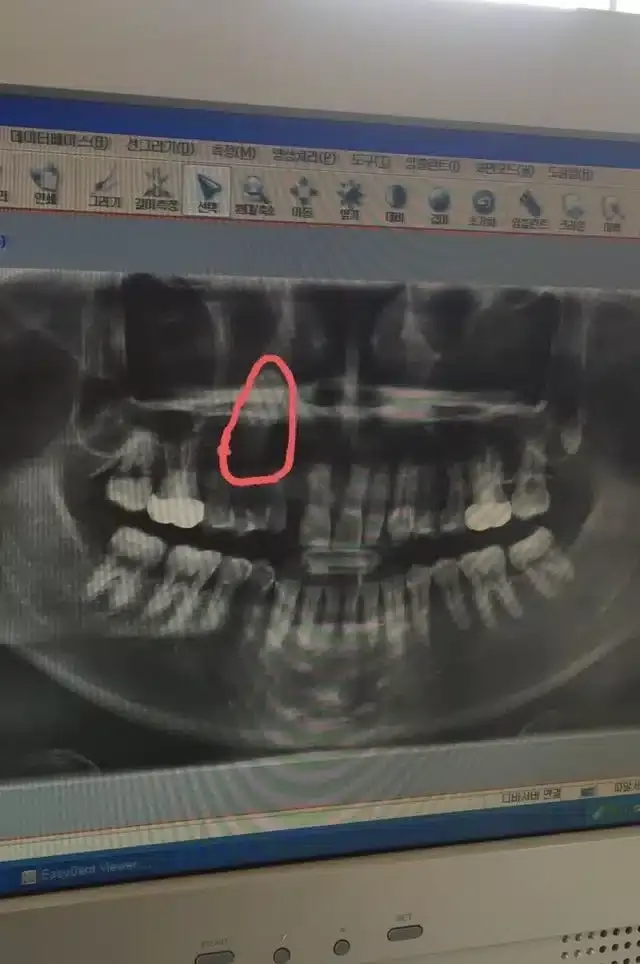

하필 치아 위치가,,